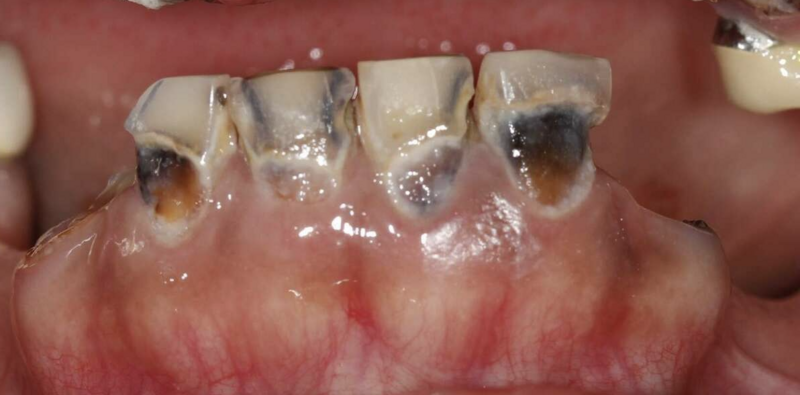

Avant

Zircone - traitement au cabinet du Dr COURONNE à Gap

Zircone - cas clinique Dr COURONNE à Gap